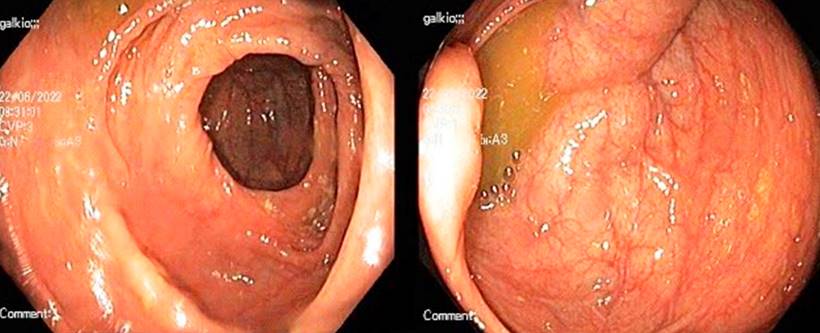

A los 6 meses manifestaba mejoría de los síntomas respiratorios y constitucionales, pero ingresó al servicio hospitalario por persistencia de dolor abdominal y diarrea. Se confirmó adherencia a la terapia antituberculosa y los estudios microbiológicos para TB fueron negativos. Entre los laboratorios realizados tenía calprotectina fecal de 2060 μg/g (Tabla 1) y en la enterorresonancia, suboclusión intestinal en el íleon (Figura 1). Se realizó una nueva ileocolonoscopia que identificó pliegues cecales, orificio apendicular y válvula ileocecal con edema grave cubierto de úlceras con sangrado fácil y edema que comprometía el colon ascendente proximal. Además, se tomaron biopsias que reportaron enfermedad inflamatoria intestinal con ulceración crónica y granulomas (Figura 2). Se hizo el diagnóstico de EC con un índice de actividad de enfermedad de Crohn (CDAI) de 421 puntos, controvertidamente se decidió postergar los corticoides y se inició el tratamiento con azatioprina.

Figura 1 Enterorresonancia con contraste. A. En fase arterial: engrosamiento del íleo (+). B. En fase portal: engrosamiento del íleo con pared de 13 milímetros. Imagen propiedad de los autores.

Figura 3 Imágenes de colonoscopia del paciente sin evidencia de actividad de la enfermedad. Imagen propiedad de los autores.